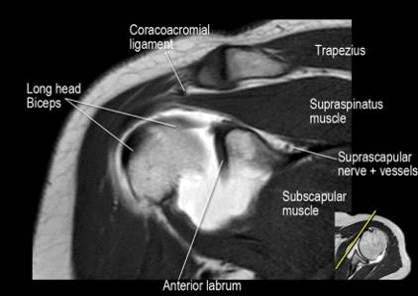

Рис. 5 Нормальная анатомия плечевого сустава в аксиальной проекции

В аксиальной проекции определяются повреждения костей и хрящей,

образующих плечевой сустав

Рис. 7 Нормальная корональная анатомия плечевого

сустава

В этой проекции оценивается клювовидно-ключичная

связка (coracoclavicular ligament) и короткая головка двуглавой мышцы (short

head of the biceps), коракоакромиальная связка, надлопаточный нерв и сосуды,

можно найти импинджмент надостной мышцы за счет остеофитов в акромиально

ключичном суставе или из-за утолщения клювовидноакромиальной связки, скопление

жидкости в подакромиальной сумке и повреждение сухожидия надостной мышцы,

подгубный карман илм SLAP-повреждение, разрыв сухожилия надостной мышцы в месте

его прикрепления в виде кольцевидного повышения сигнала